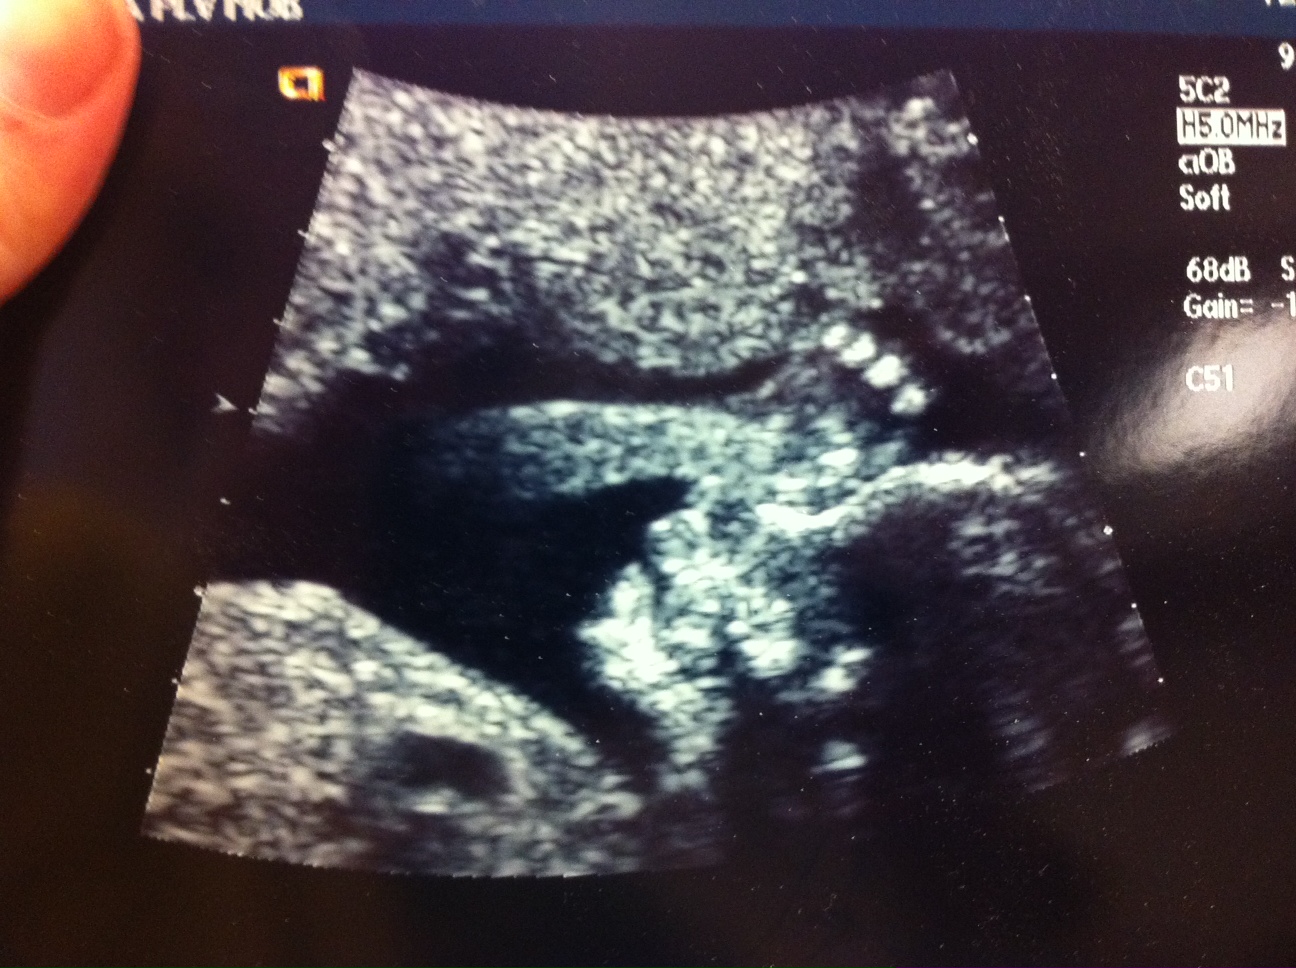

Here’s our new little baby. You can see her right hand and fingers, a side view of her head, and her heart(that black blob in her chest). She should arrive around September 24th.